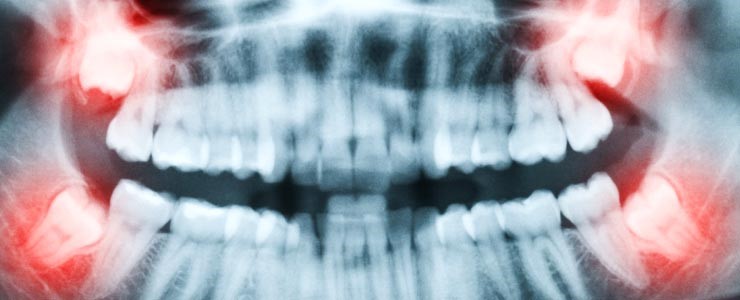

At Springhill Dental, our dentist in NW Calgary can take diagnostic images via our digital radiographs (x-rays) to assess what is going on underneath the gums and to help determine if the wisdom teeth need to be extracted and to determine what is the safest method to remove them.

Before removal, your dentist will review your X-rays and explain the plan for the procedure. The tooth is then carefully removed, and the area is cleaned to support healing. If needed, stitches may be placed. You’ll receive clear aftercare instructions before you leave so you know how to care for the area at home.